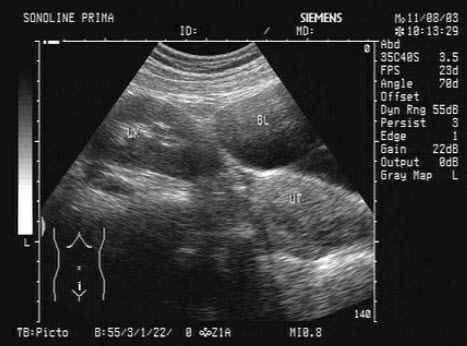

2、单项选择题 超声对多大的膀胱肿瘤难以检出()

A.1cm

B.2cm

C.0.5cm

D.1cm和2cm

E.1cm和0.5cm